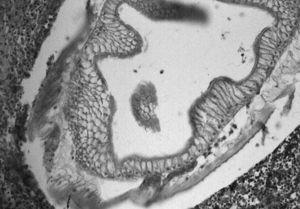

Varón de 63 años que presenta dolor abdominal difuso e intenso, asociado a náuseas, vómitos y fiebre. El paciente manifestó que había ingerido boquerones (Engraulis encrasicholus) en vinagre 3 días antes. En la exploración destacaba un abdomen distendido, timpanizado con peritonismo generalizado. La analítica revelaba leucocitosis con neutrofilia y en la tomografía computarizada (TC) abdominal se apreciaba un segmento de íleon distal de unos 15 cm muy engrosado, con asas intestinales proximales muy dilatadas, abundante líquido intraperitoneal y engrosamiento del antropíloro. En la intervención quirúrgica se objetivó una zona de ileítis perforada con un exudado fibrinopurulento sobre una serosa muy congestiva. Se resecó el segmento afectado, cuyo examen macroscópico reveló la presencia de un parásito (fig. 1; punta de aguja) en una zona fisurada de la mucosa. Existía, además, un importante edema transmural con múltiples erosiones y petequias en la mucosa. El examen histopatológico confirmó la presencia transmural de un parásito tipo Anisakis sp., así como un importante edema e infiltración periparasitaria y transmural de neutrófilos, eosinófilos, linfocitos y células plasmáticas (fig. 2).

Figura 2.

En la anisakiasis de tipo intestinal, que representa hasta un tercio de los casos, la reacción inflamatoria como consecuencia y respuesta contra el parásito puede condicionar un cuadro obstructivo; no obstante, la posibilidad de perforación intestinal, principalmente ileal, es un hecho constatado en la bibliografía.